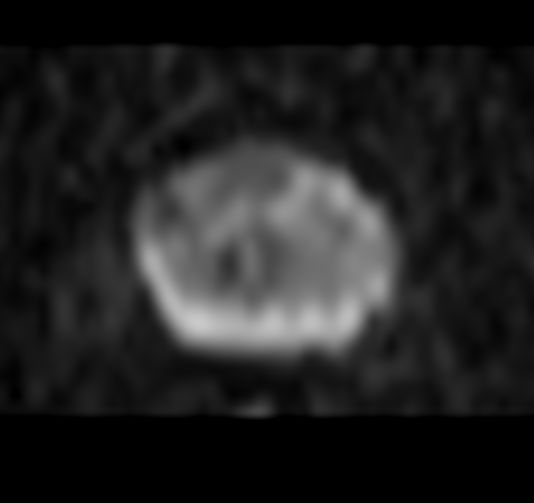

Comparisons of DWI sequences are included with maximum gradient strength versus enhanced gradient strength (45 mT/m, 220 T/m/s). Higher gradient specifications means more signal-to-noise in higher b values.

Axial DWI b100Gradient strength: Maximum

Axial DWI b1500Gradient strength: Maximum

Axial DWI b2000Gradient strength: Maximum

Axial DWI b100Gradient strength: Enhanced

Axial DWI b1000Gradient strength: Enhanced

Axial DWI b2000Gradient strength: Enhanced